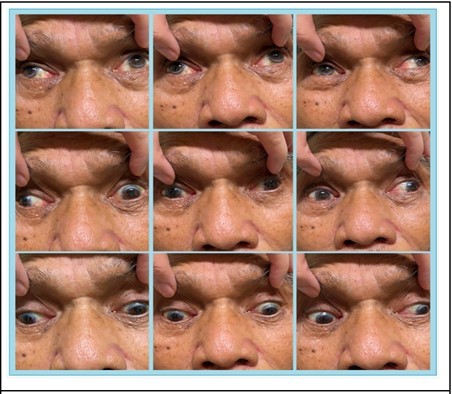

The patient was then referred to the Ophthalmology Service at the ER level. At that time the VA of the patient was 6/10 on both eyes, unremarkable anterior segment findings with an NO4 NC4 cataract for both eyes and unremarkable funduscopic findings.Patient had bilateral exotropia in primary gaze with the pupillary light reflex on the nasal limbus of both eyes on Hirschberg. (Figure 1). Patient had bilateral adduction deficits in both version and duction tests.Other cranial nerves were intact.

Figure 1.Bilateral exotropia on primary gaze exotropia and bilateral adduction deficit during version

Figure 2.There was persistence of bilateral adduction deficit on duction testing

Figure 3.No convergence of both eyes were noted

The patient was referred back to Ophthalmology service after 4 days. The patient was conscious, coherent, oriented to three spheres, wheel chair borne. At this time, there was persistence of diplopia but there was no dizziness. The BCVA of the patient was 6/7.5 both eyes. Ishihara was 14/15 for both eyes, with persistent bilateral exotropia in primary gaze. Exotropia was measured at 30 prism diopters on Krimsky and unchanged bilateral adduction deficits in both version and duction tests. (Figure 4)

Horizontal nystagmus of the abducting eye and gaze evoked vertical nystagmus on both eyes were noted. (Video 1 and 2) The adduction deficit was not overcome with either doll’s head maneuver and with an accomm dating target. (Figure 5) Forced duction testing was done and there was no restriction on both eyes noted.